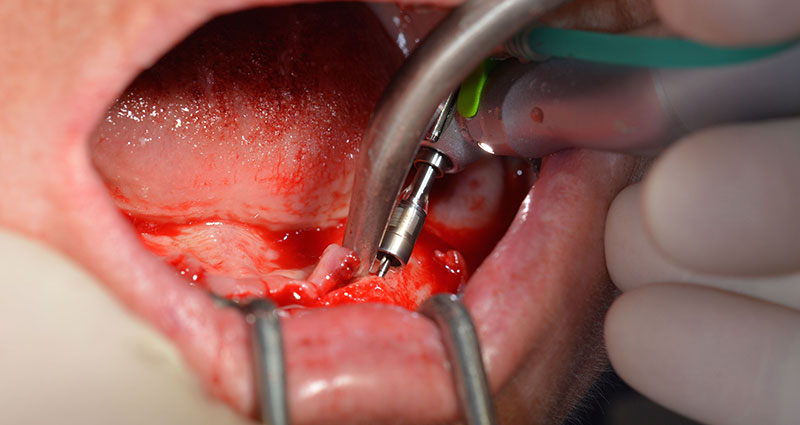

Tras la extracción de la dentición residual en el maxilar inferior, se realizó la incisión crestal en la región comprendida entre la pieza dental 37 y la 47.

A continuación, se identificó el agujero mentoniano (foramen mentale) como la estructura anatómica límite y se alisó el cortical de la cresta ósea con la pieza de mano recta y una fresa redonda grande (fig. 4).